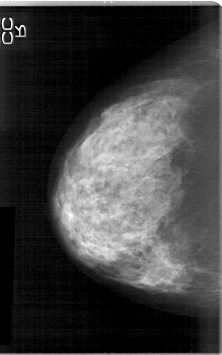

D_4114_1.RIGHT_CC

RIGHT_CC LINES 5311 PIXELS_PER_LINE 3316 BITS_PER_PIXEL 12 RESOLUTION 43.5 NON_OVERLAY